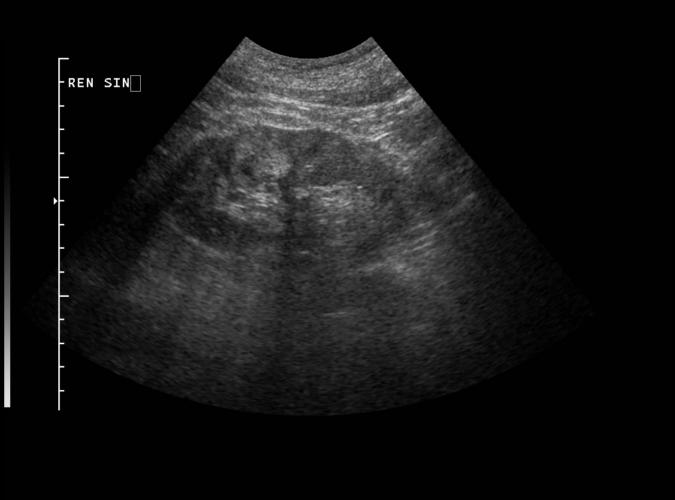

Patologi.

Long. vänster njure. Adenocarcinom utan påverkan på

njurkonturen.